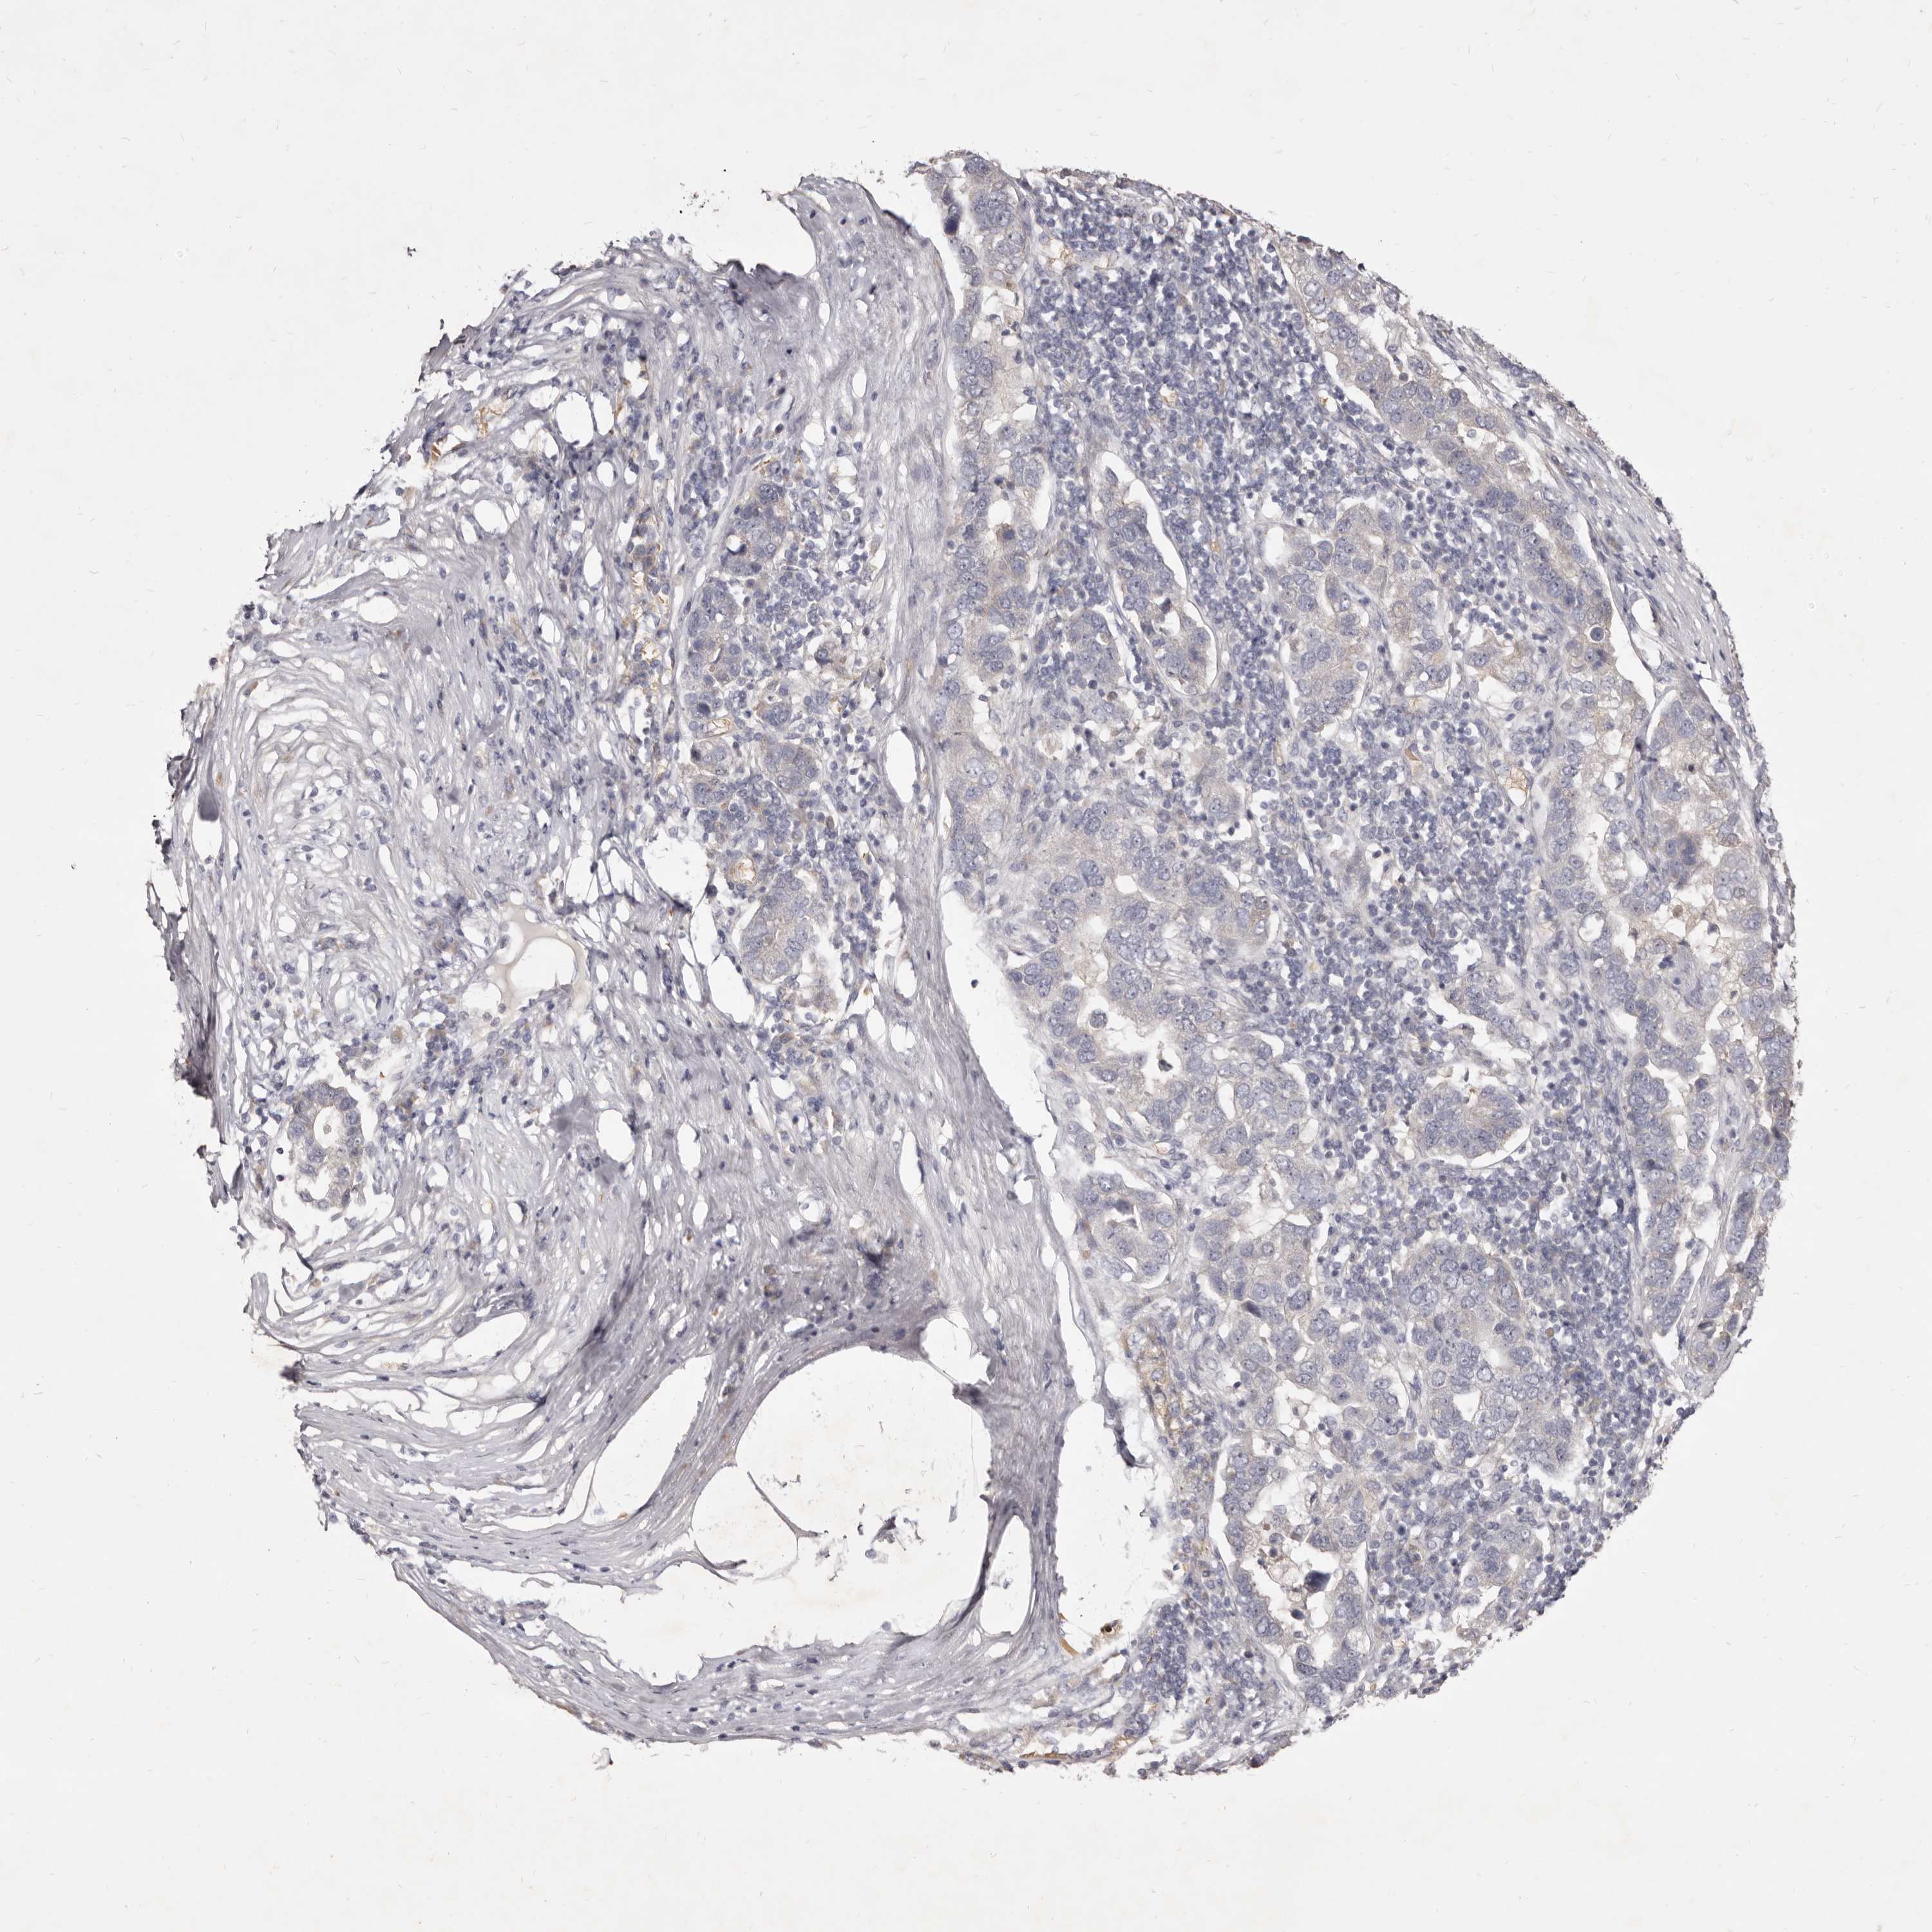

PANCREATIC CANCER - Protein expressioni

A mouse-over function shows sample information and annotation data. Click on an image to view it in a full screen mode. Samples can be filtered based on level of antibody staining by selecting one or several of the following categories: high, medium, low and not detected. The assay and annotation is described here.

Note that samples used for immunohistochemistry by the Human Protein Atlas do not correspond to samples in the TCGA dataset.

Antibody stainingi

Antibody staining in the annotated cell types in the current human tissue is reported as not detected, low, medium, or high, based on conventional immunohistochemistry profiling in selected tissues. This score is based on the combination of the staining intensity and fraction of stained cells.

Each image is clickable and will lead to virtual microscopy that enables deeper exploration of all samples and also displays staining intensity scores, fraction scores and subcellular localization as well as patient and tissue information for each sample.

Antibody HPA023081

Antibody HPA023103

Antibody HPA024795

Staining

High

Medium

Low

Not detected

Intensity

Strong

Moderate

Weak

Negative

Quantity

>75%

75%-25%

<25%

None

Location

Nuclear

Cytoplasmic/membranous

Cytoplasmic/membranous,nuclear

Adenocarcinoma, NOS